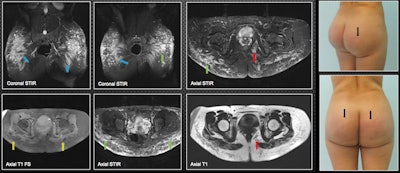

MRI provides the most information to the radiologist and should be done on all patients, they stated. "It can warn the surgeon about the level of tissue compromise. It shows the affected planes and the approximate amount of biopolymers injected. It demonstrates their areas in the case of material migration."

Additionally, MRI presents the biopolymer in encapsulated form (rounded-oval or elongated vesicles). The round and elongated vesicles can be seen affecting the subcutaneous cellular tissue, so the location is superficial, while the elongated ones are found on deep planes, infiltrating the gluteal fibers.

"Regarding the most frequent areas of migration, we have found that soft tissues of the lumbosacral region are the most frequent, followed by the bilateral ischiorectal region, female external genitalia, and lower limbs," they noted.

A few weeks after placing the biopolymers, liquid forms can be seen that simulate seromas without vesicles. After six to 12 months, seromas and vesicles coexist. After more than 18 months, only vesicles containing the biopolymer material are found. In many patients, there is migration from deep to superficial planes, which, due to their shape and distribution, suggests that lymphatic drainage has occurred.

The length of time that patients carry the biopolymer in the buttocks plays an important role in the way the material will be presented in tissues, the authors wrote.